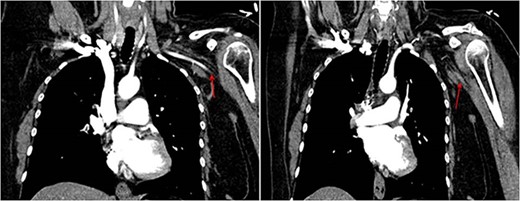

A 45-year-old female patient with a personal history of hypothyroidism, obesity, inferior parathyroidectomy for parathyroid adenoma and adnexectomy for benign ovarian cystadenoma presented with sudden onset dyspnoea as well as with pain, poikilothermia, pallor and weakness of left upper limb and hand. Physical examination showed peripheral O2 saturation of 80% and absence of radial and left brachial pulses. On Duplex ultrasound, deep or superficial vein thrombosis was not identified. On thoracic computed tomography angiography, bilateral pulmonary embolism (PE) and occlusion of the axillary artery were identified while aortic dissection was excluded (Fig.1). Given the concomitant upper limb ischemia and PE, the patient was hypocoagulated with low-molecular-weight heparin and underwent urgent thromboembolectomy and angiography, through a distal brachial surgical approach. Postoperatively, the patient recovered a radial and ulnar pulses. The embolic source was further investigated by transthoracic and transesophageal echocardiography, which identified a PFO (Fig.2). The patient was discharged on rivaroxaban for anticoagulation (20 mg once daily). During follow-up, thrombophilia screening was performed, including antiphospholipid antibody syndrome, factor V Leiden mutation, prothrombin gene mutation, antithrombin III defect, protein C and S deficiency assessments, but all results were negative. Considering the single event of right atrioventricular overload and flow-inversion through PFO associated with PE, PFO closure was not indicated.